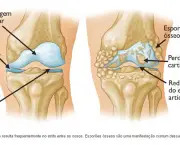

O desenvolvimento dessa doença se dá pelo desgaste das cartilagens responsáveis por revestir as extremidades ósseas de forma a causar muita dor e até mesmo deformações. A incidência de Artrose no Joelho é bastante comum porque as articulações do joelho estão dentre as articulações mais afetadas pela sobrecarga de peso.

O principal sintoma que a Artrose no Joelho apresenta é a dor constante, essa dor tende a piorar quando é feito um grande esforço ou mesmo com a rigidez matinal das articulações comprometidas. O indivíduo pode ter alguma dificuldade em apoiar o seu peso no joelho que sofre com o problema.

Outro sintoma bastante significativo desse problema nos joelhos é sentir um tipo de crepitação quando faz algum movimento com os joelhos. Devido ao crescimento de ossos ao redor do joelho o indivíduo sente que o joelho está inchado. Quando uma pessoa começa a sentir além de dores nos joelhos perda de sua função (de aguentar carga) deve procurar por um especialista.